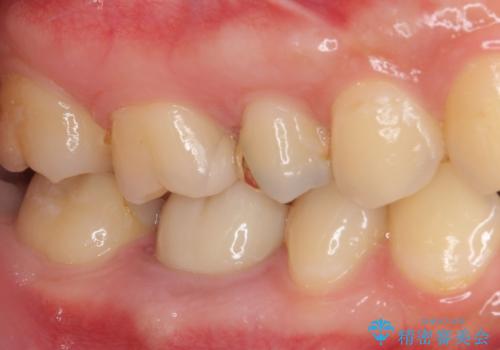

- 奥歯の銀歯の下にあるむし歯治療を希望して来院された患者様です。

口を開けたときに見えてしまう部分はセラミックインレーやジルコニアクラウンに、目立たない部分はゴールドインレーにてむし歯治療を行うこととしました。

機能面を優先すると、PGAインレー(ゴールドインレー)による修復治療やPGAクラウンによる補綴治療が望ましいのですが、笑ったときに見えている銀歯がどうしても気なってしまうとのことで、目立ってしまう奥歯はセラミックインレーやセラミッククラウンを装着することとしました。

見た目を気にすることなくむし歯治療を行うことができ、患者様に大変満足していただきました。